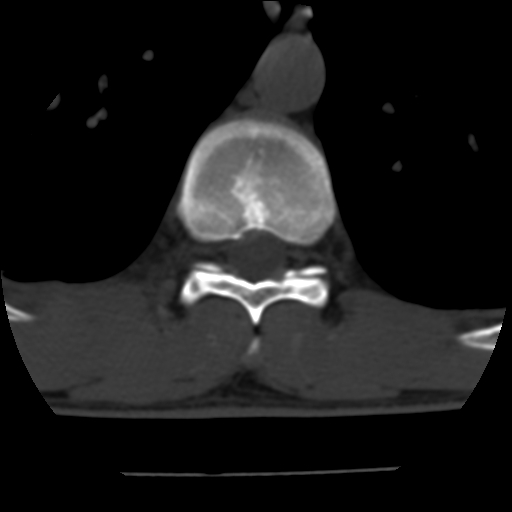

标题: CT10387:男,31岁,胸腰段CT [打印本页]

标题: CT10387:男,31岁,胸腰段CT

男,31岁,从6米高处坠落伤两天,腰背部疼痛,临床要求ct扫描胸10-腰1。请大家帮忙看看骨质有问题吗?

t12、l1锥体前缘轻度楔形变,平扫示椎体前缘骨小梁欠规整,第9幅图示椎体前缘骨质不连续,结合外伤史考虑椎体轻度压缩骨折。

楼主扫描层厚可能较大,每个椎体只有三个层面.

从所示层面分析,无明确骨折征象,象类似病人我个人会建议mri除外骨挫伤.

从上查骨窗第九片椎体前缘皮质显示断裂.压缩骨折?